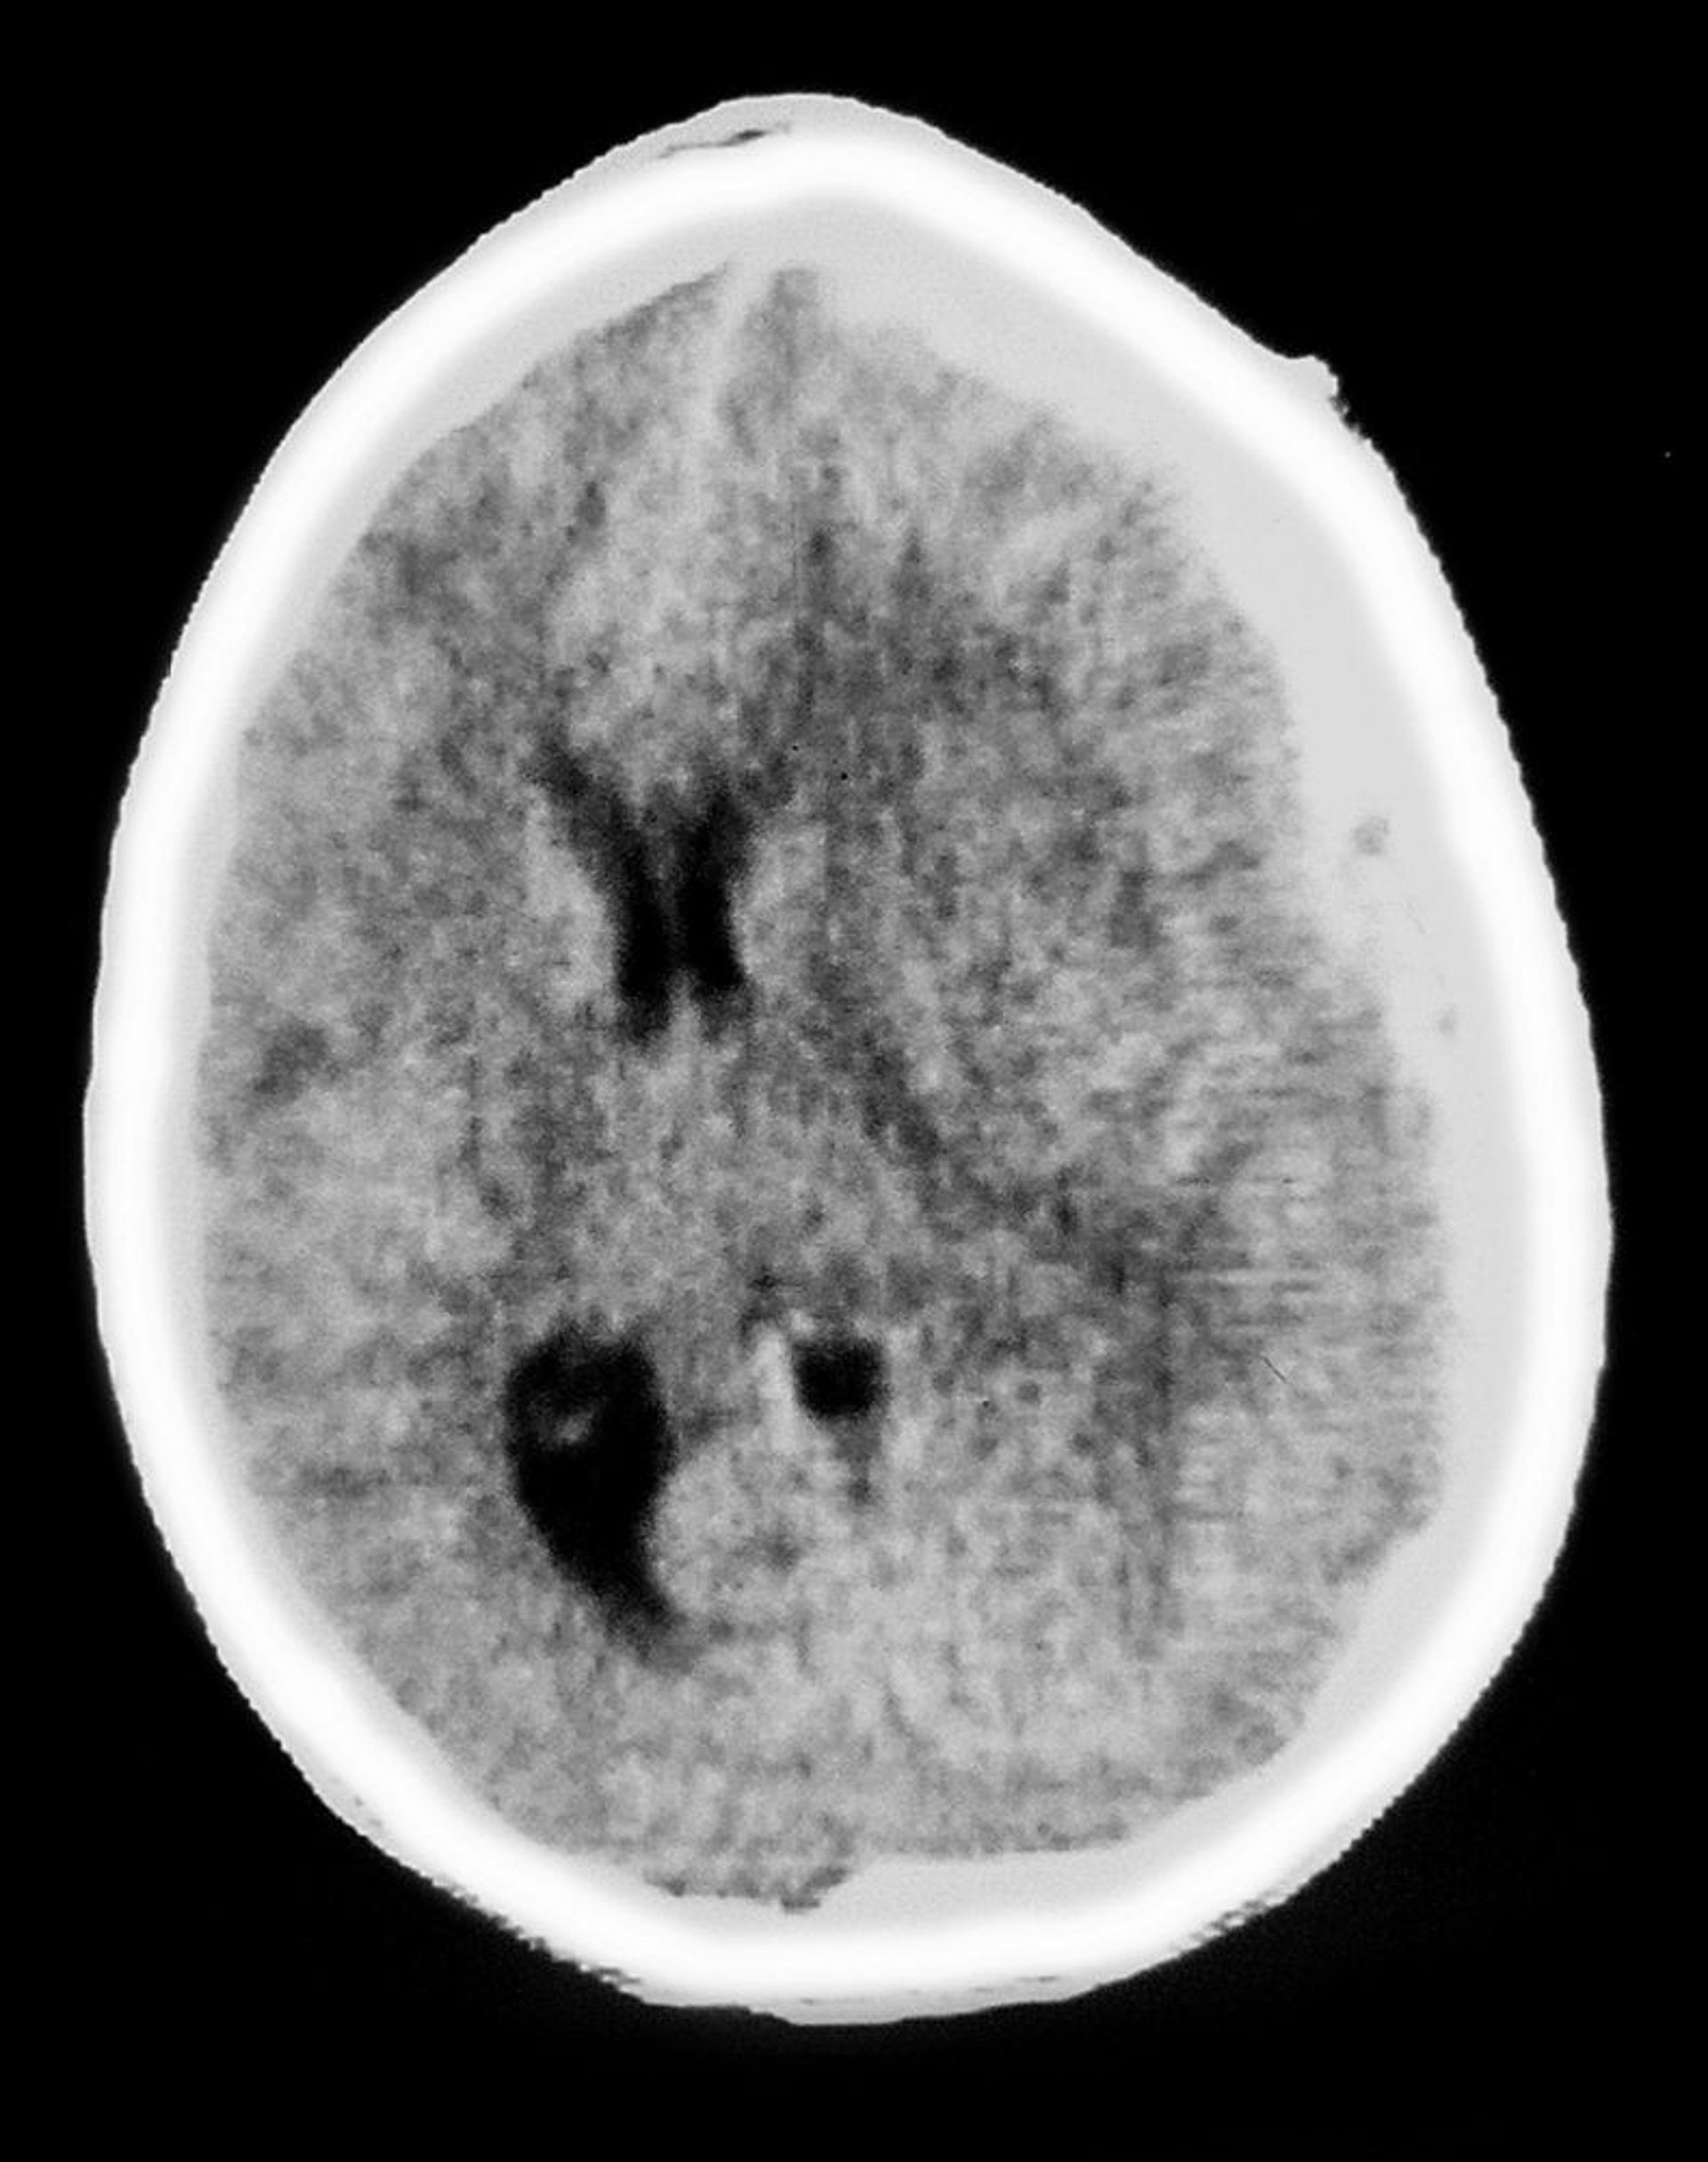

Субдуральна гематома

На цьому КТ-скані зображено непрозорі, характерні для субдуральної гематоми ділянки у формі півмісяця, що розташовуються над тканинами головного мозку. Також спостерігається виражений мас-ефект зі стисненням шлуночків та зміщенням серединних структур.

Кавалліні Джеймс (Cavallini James) / BSIP / НАУКОВА ФОТОБІБЛІОТЕКА